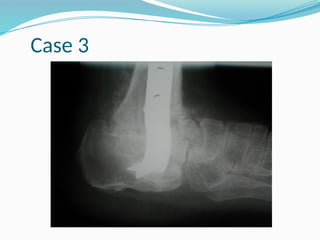

Case 3